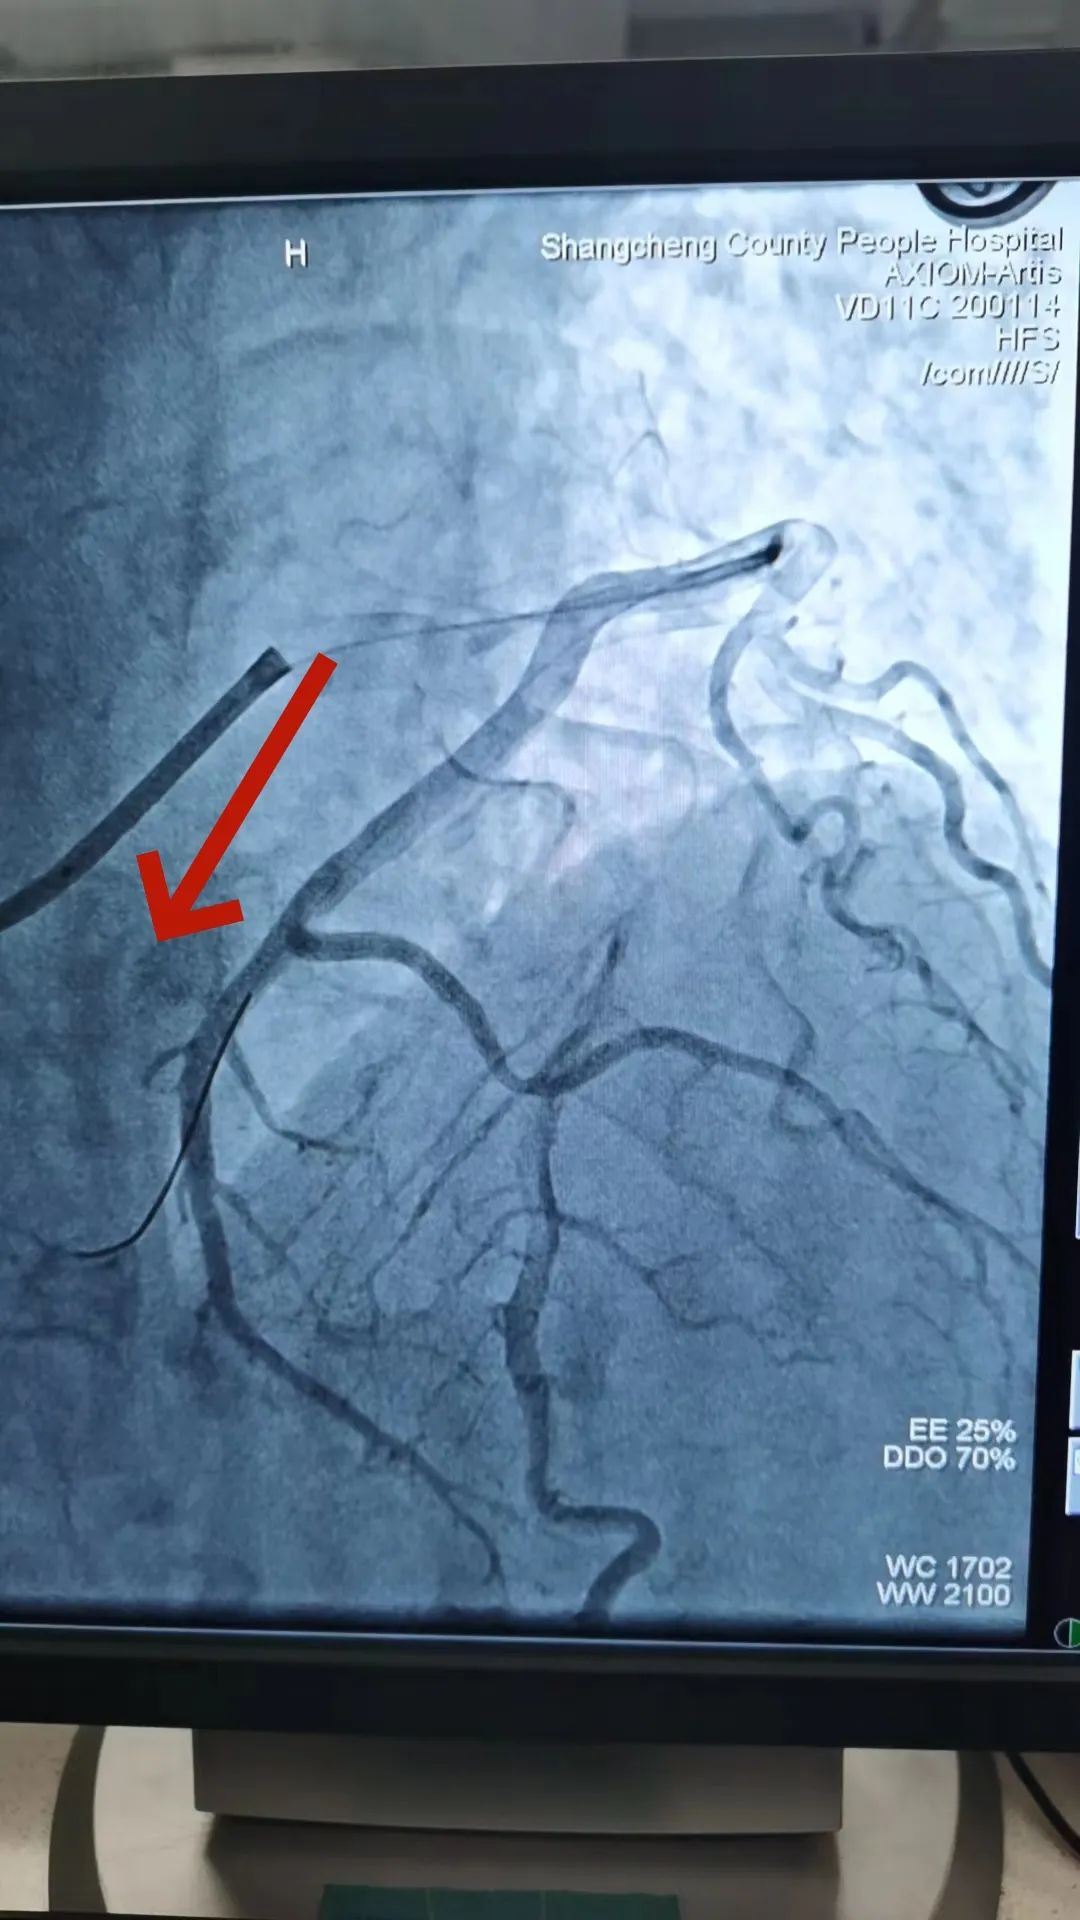

1697763870661024.jpg

回旋支远端完全闭塞

此时,患者的胸痛症状丝毫没有缓解,复查心电图显示下壁导联ST段仍持续抬高。患者病情刻不容缓,经过短暂思考后,熊主任当机立断:尝试开通回旋支远端血管!在熊主任的指导下,刘燃医师小心翼翼的置入预扩球囊扩张回旋支远端,果然发现左旋支直径2.5mm,是右心供血功能血管。但是血管扩张后患者突然出现心率减慢、血压降低的现象,面对这种突发状况,熊主任考虑患者是再灌注后血管痉挛、心律失常,刘医生立即向冠脉内注射硝酸甘油200μg,随后患者心率、血压回升到正常。在进行重复造影后可见患者回旋支远段粗大且长,延伸至右心,再次确定回旋支远端为“罪犯血管”。经过球囊扩张手术后,血管狭窄解除,血流3级,心电图提示下壁导联明显回落,胸痛症状明显缓解,手术有效,抢救成功!